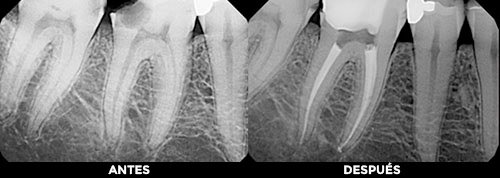

ENDODONCIA

El tratamiento de endodoncia está diseñado para retirar el nervio y eliminar las bacterias que se encuentran dentro de la raíz del diente infectado y por este medio lograr salvar el órgano dental.

Cuando se realiza la endodoncia, se extrae el nervio inflamado o infectado y el interior del diente se limpia y desinfecta cuidadosamente para sellarlo con material estéril, quedando listo para ser restaurado por medio de una corona, incrustación o resina, según sea el caso.

Salvar el diente natural con un tratamiento de endodoncia tiene muchas ventajas:

- Se elimina la infección del órgano dentario.

- Se salva el diente de una extracción.

- Elimina dolor.

- Masticación eficiente.

- Fuerza y sensación normal al morder.

- Apariencia natural.